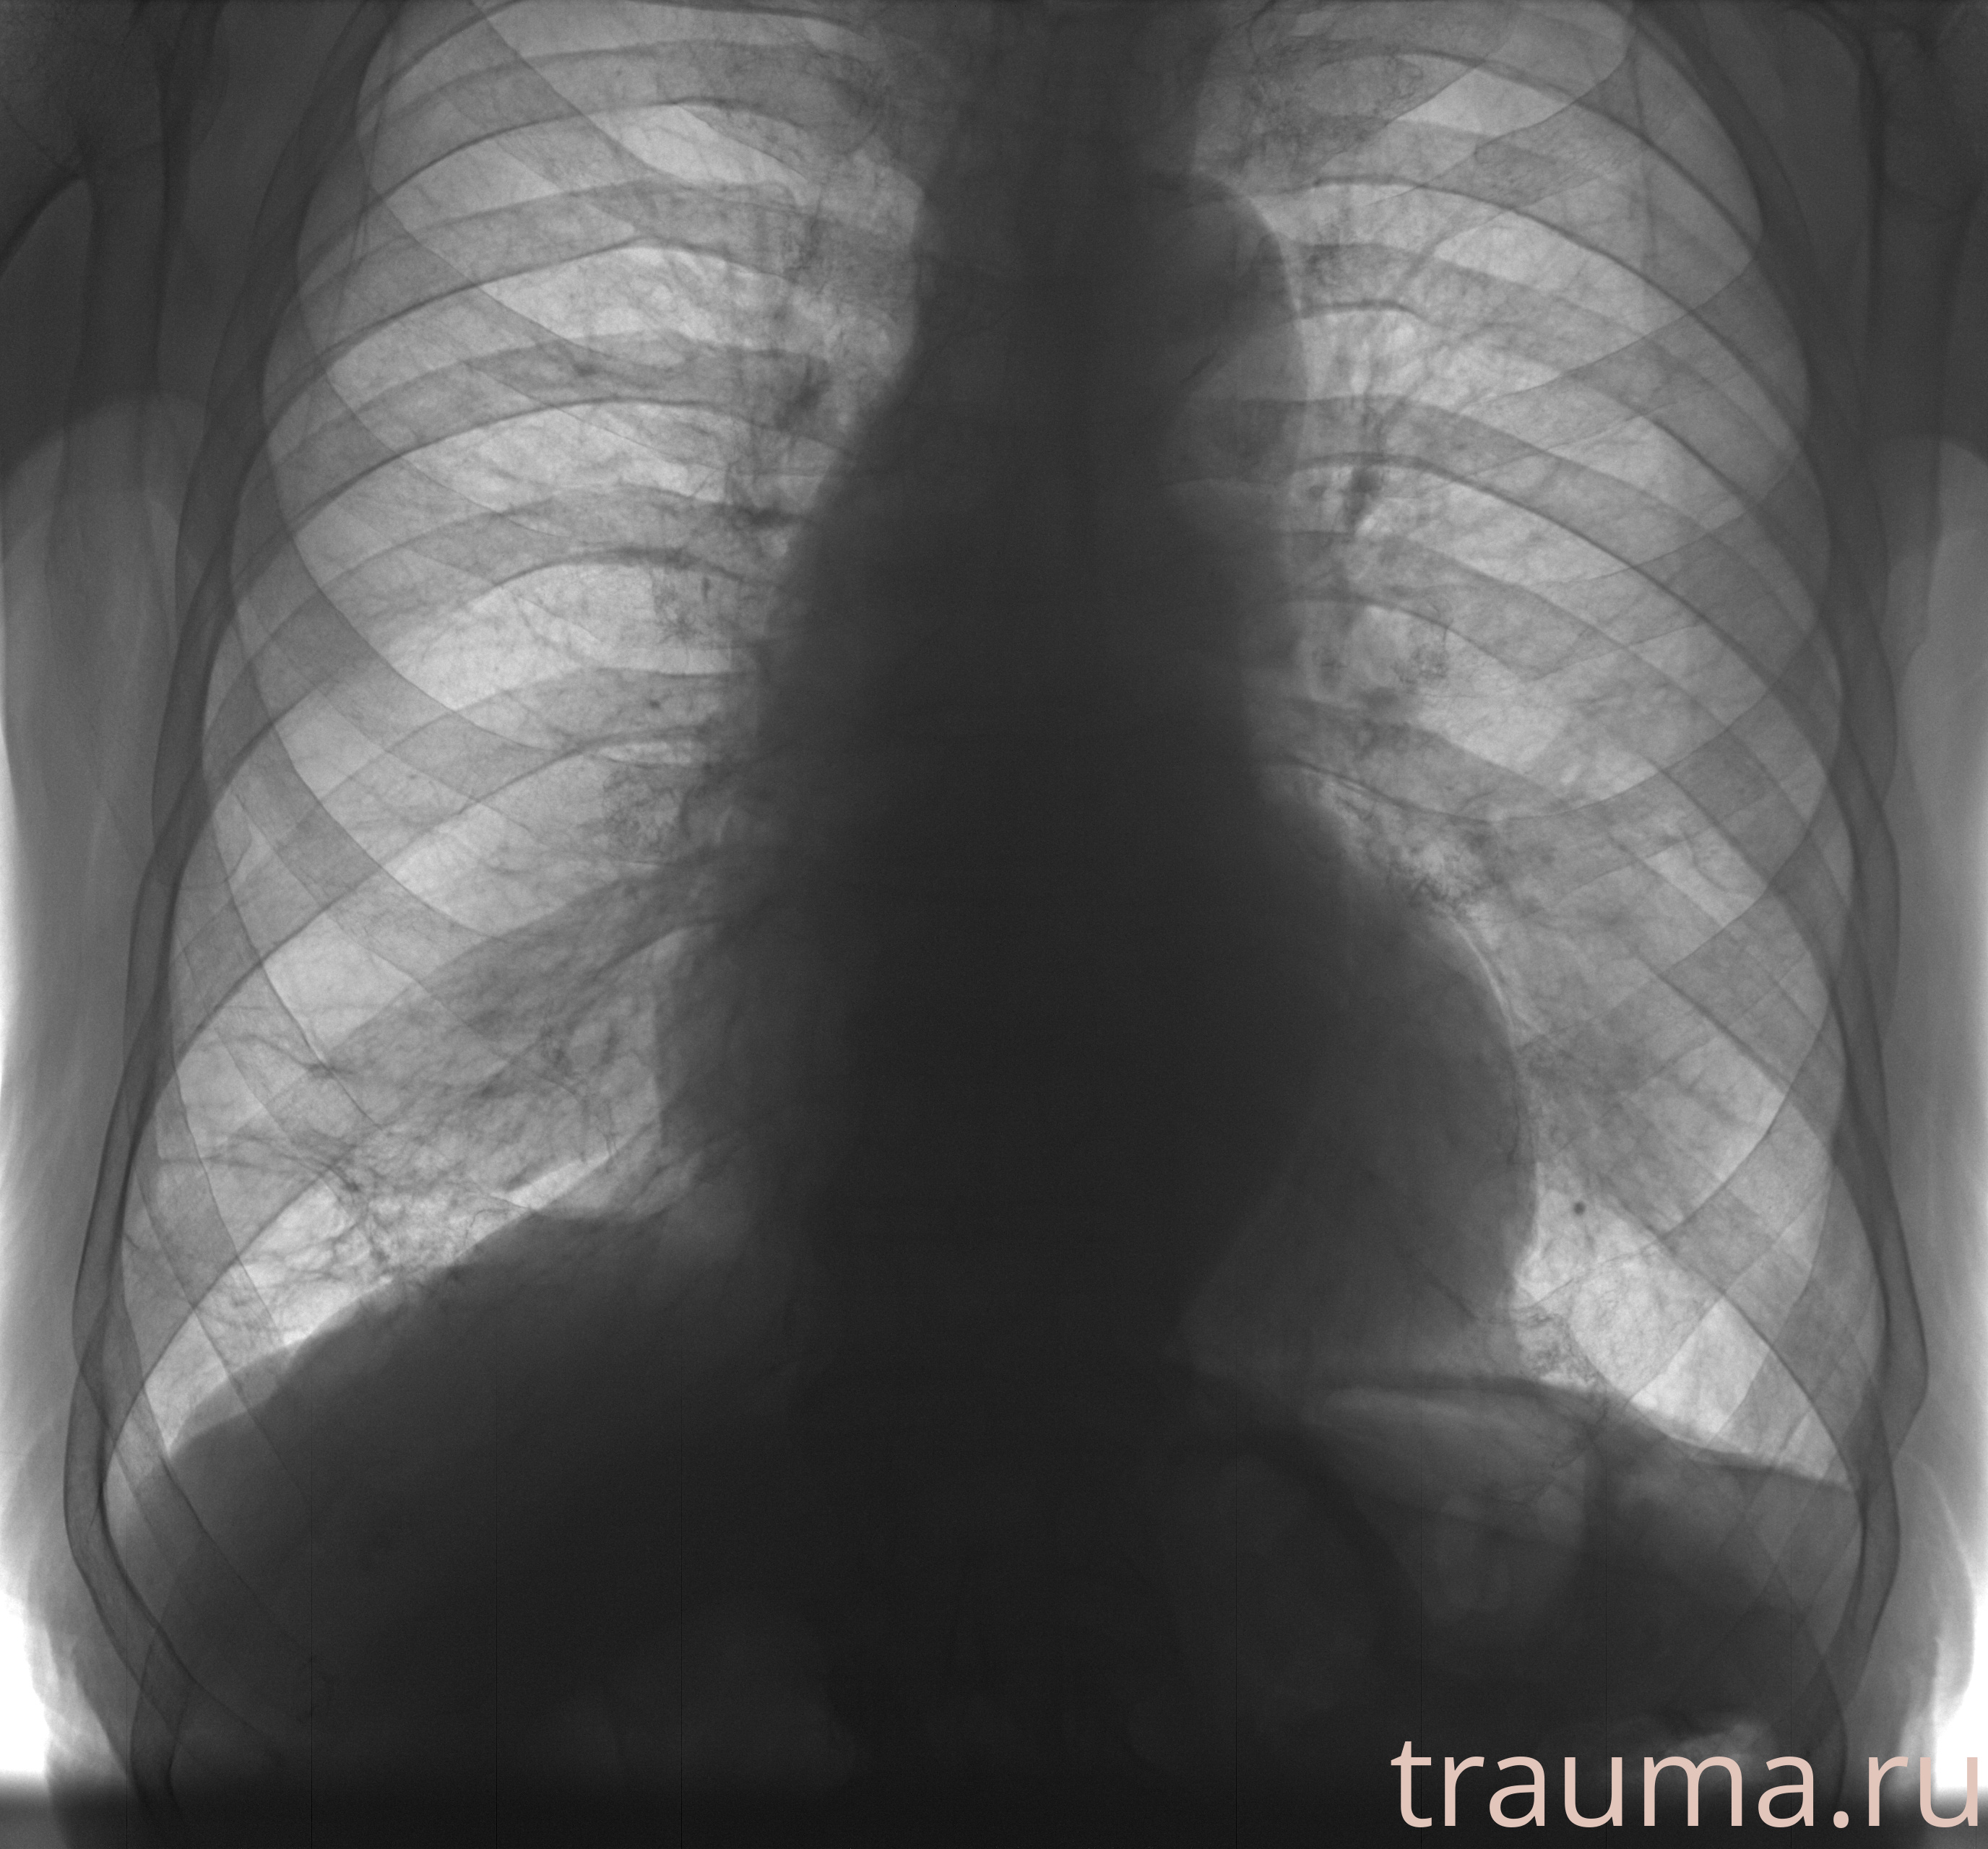

Рентген на дому: по вашему адресу приезжает врач-рентгенолог, травматолог-ортопед с мобильным рентгеновским аппаратом, проводит диагностику травмы или заболевания, делает необходимые рентгенограммы, дает рекомендации по дальнейшему лечению. Получить качественные снимки в домашних условиях возможно благодаря уникальной методике, разработанной МосРентген Центром для института  Склифосовского

при переломе шейки бедра и пневмонии от компании МосРентген Центр - партнера Института имени Склифосовского